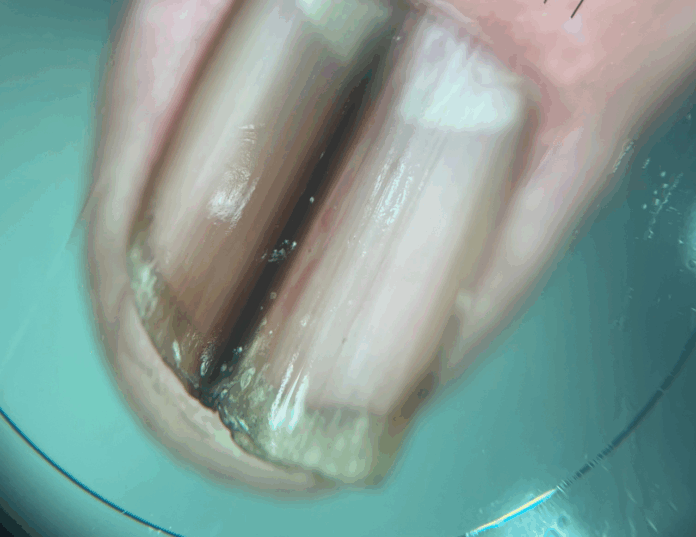

“El cáncer de uña se puede manifestar a través de un cambio de color o textura en un único dedo, una lesión verrugosa cerca de la uña, en los pliegues laterales o una herida que no cicatriza y que, con el tiempo, puede destruir la uña completamente. También debe generar sospecha una supuesta infección por hongos o bacterias que no mejora pese a tratamientos prolongados. Otra cosa muy importante es que aparezca una mancha lineal de color café oscuro o negra, llamada melanoniquia, que también puede ser un signo de alerta y una alta sospecha de melanoma”, aclara el especialista.

- Cambio de color o textura de la uña.

- Mancha lineal negra o café oscuro.

- Herida o erosión bajo la uña.